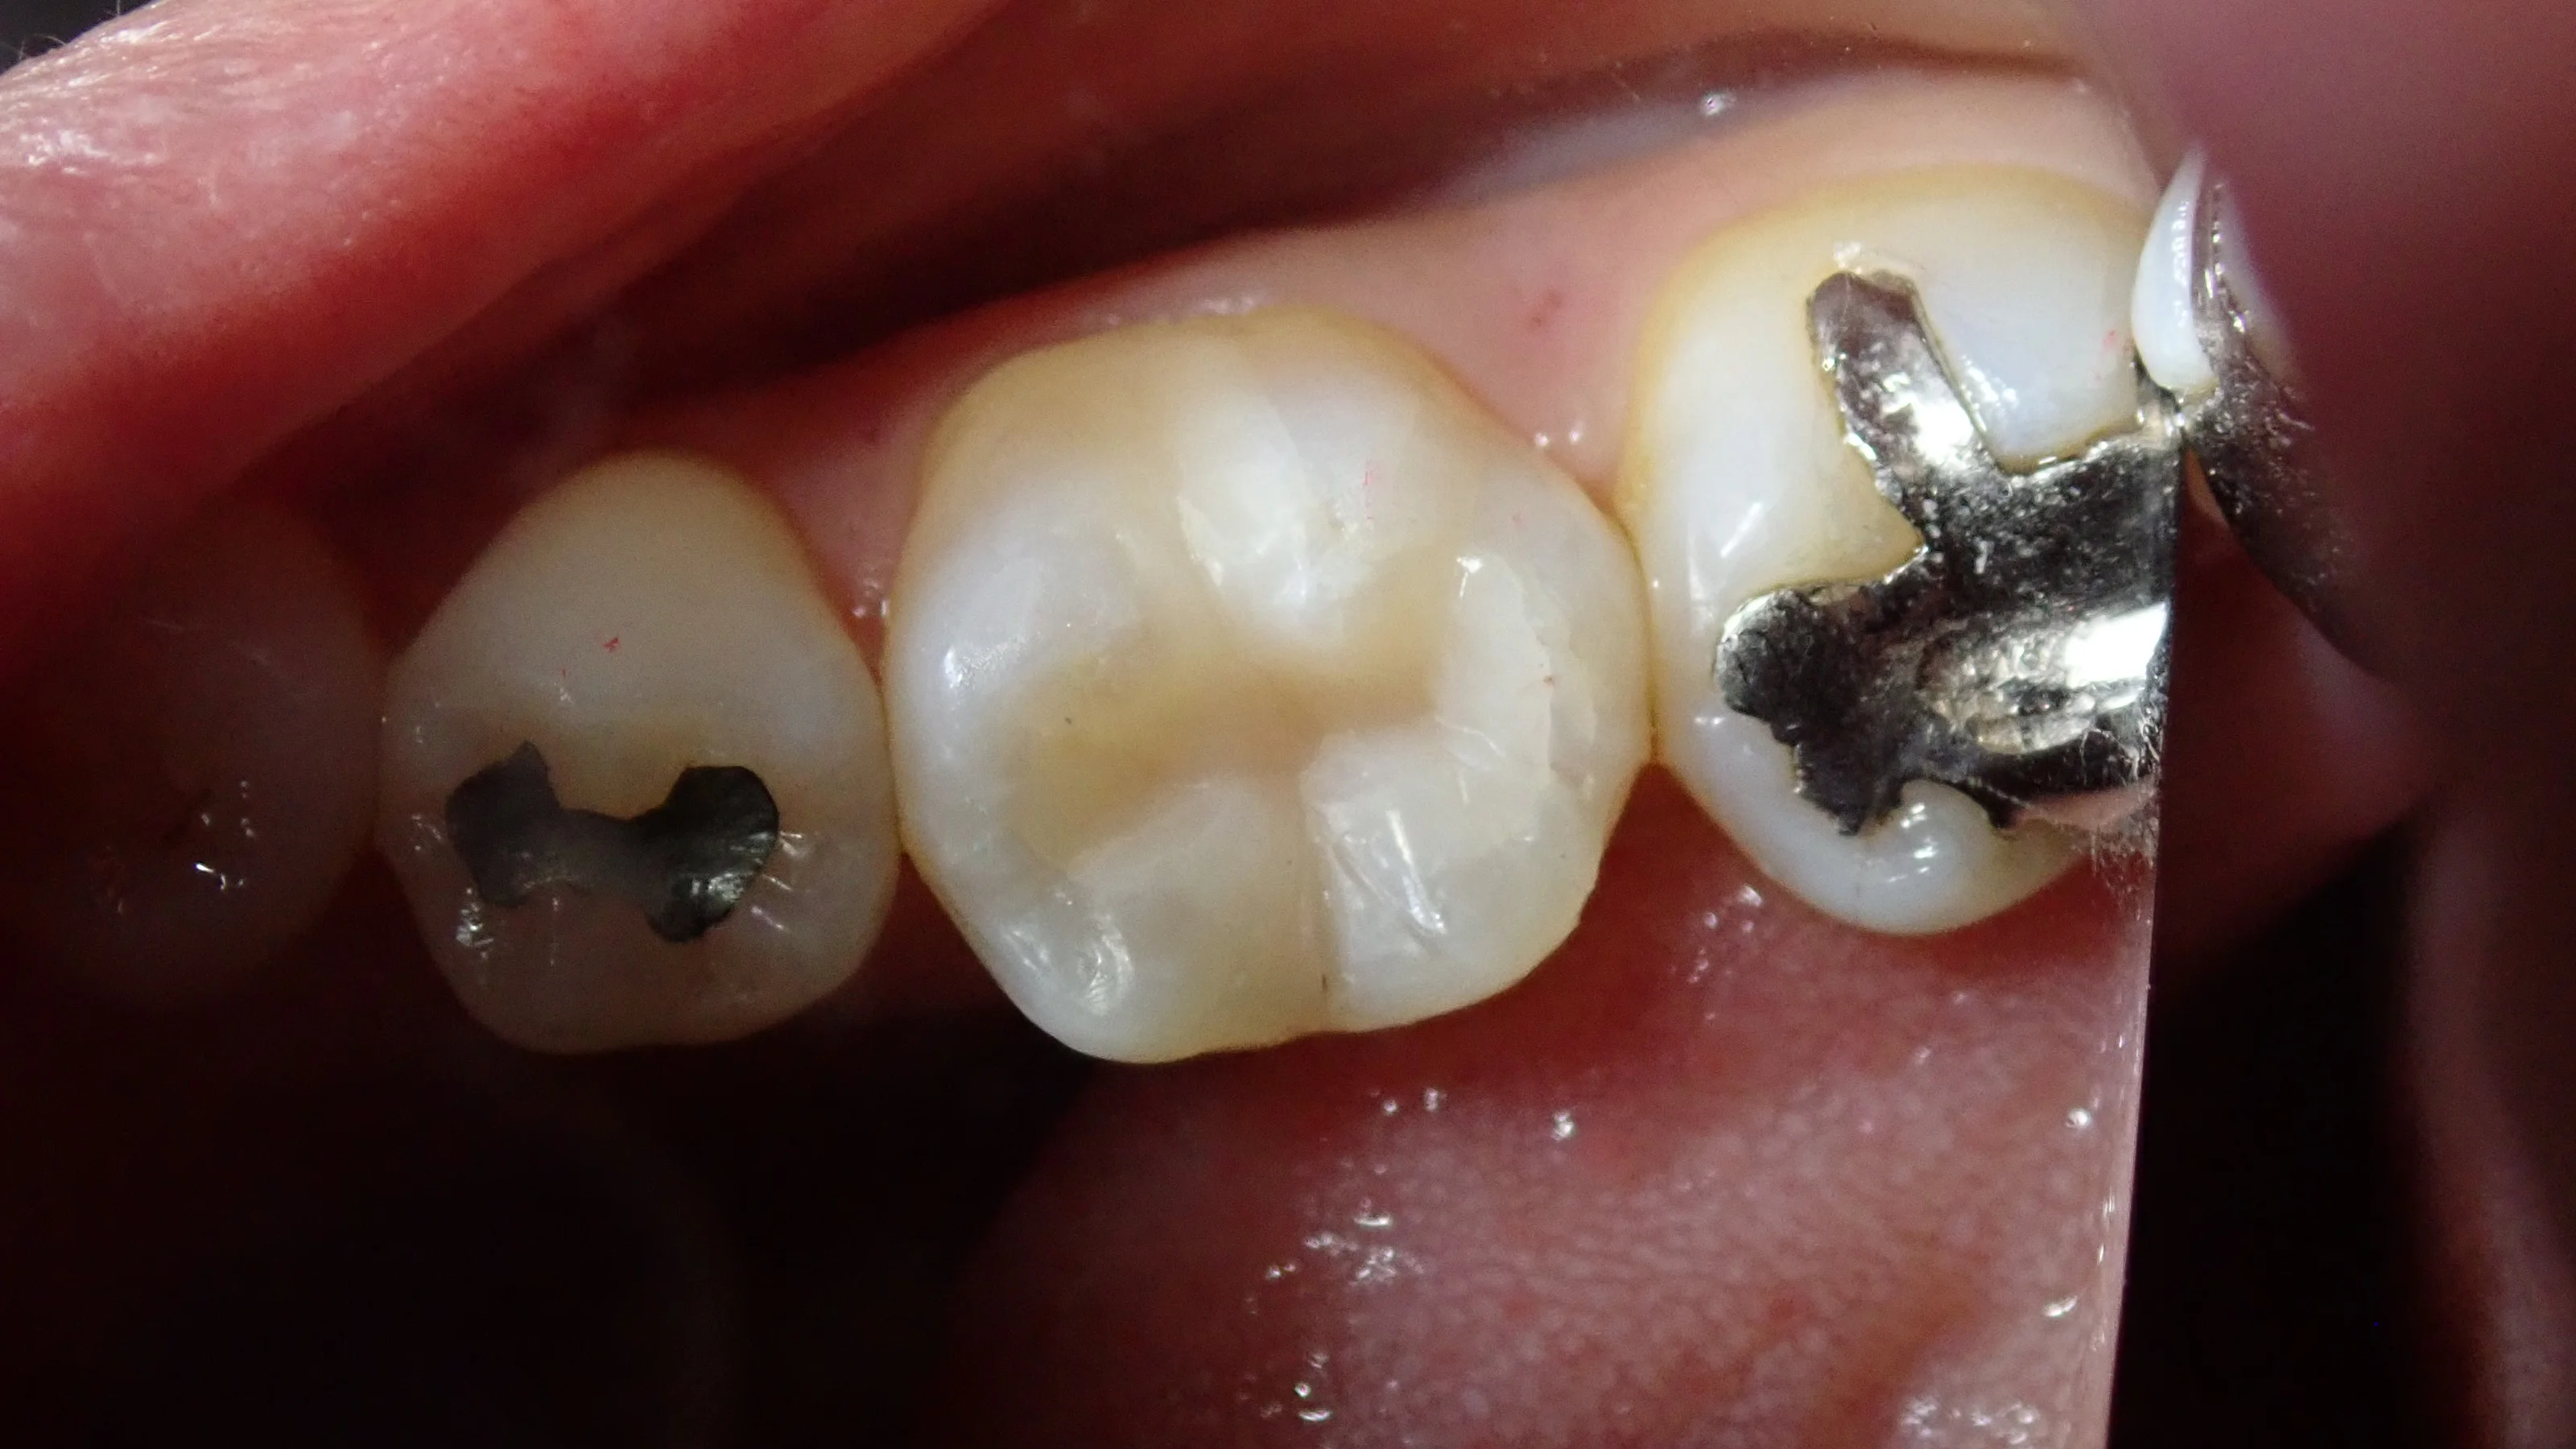

まずは術前ですね。

コンポジットレジン|坂寄歯科医院(取手市藤代)

咬む力の加わらない外側に器用に金属が詰められており、噛む力の加わる噛む面に保険のコンポジットレジンが詰められています。

その下が黒っぽいのが分かると思います。